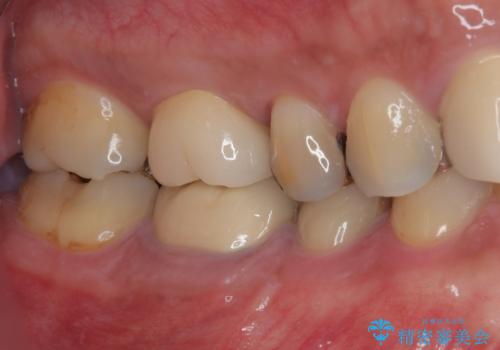

根管治療後に痛みの消失を確認し、オールセラミッククラウンにて補綴治療を行うこととしました。

初回の根管治療時に仮歯を装着しましたが、仮歯を介して食事などを行っても痛みは感じなくなっており、その後は速やかに補綴治療を行いました。